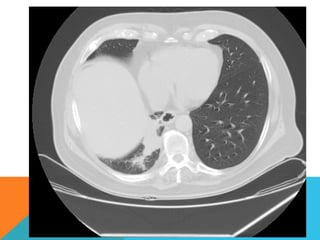

ABORDAJE TÉCNICO: Se realiza estudio con ventana mediastinal y de parénquima pulmonar con técnica de ALTA

RESOLUCION, en inspiración y espiración, mediante  cortes axiales, desde ápices hasta bases pulmonares, con las

siguientes observaciones

Ambos pulmones con neumatización conservada, con sobredistensión pulmonar, y áreas de atrapamiento aéreo,

bilateral con cambios fibrosos cicatriciales apicales derechos. Se demuestran áreas de condensación en topografía

predominantemente parenquimatosa pulmonar derecha, la mayor de ellas evidenciada hacia la base, acompañada

de broncograma aéreo, la medición máxima al corte axial de 6.1 por 2.2 cm, en topografía del segmento posterior

del lóbulo inferior, S10 así como también otra más se definen topografía de similares características en topografía

del segmento medial del lóbulo medio, S5. En topografía parenquimatosa pulmonar izquierda imagen de similares

características a las ya descritas en topografía del segmento lingular inferior, S4.

ABORDAJE TÉCNICO: Serealiza estudio con ventana mediastinal y de parénquima pulmonar con técnica de ALTA RESOLUCION, en inspiración y espiración, mediante  cortes axiales, desde ápices hasta bases pulmonares, con las siguientes observaciones En las partes blandas y las estructuras óseas dentro de los límites de la normalidad. Las regiones axilares libres. Ambos pulmones con neumatización conservada, con sobredistensión pulmonar, y áreas de atrapamiento aéreo, bilateral con cambios fibrosos cicatriciales apicales derechos. Se demuestran áreas de condensación en topografía predominantemente parenquimatosa pulmonar derecha, la mayor de ellas evidenciada hacia la base, acompañada de broncograma aéreo, la medición máxima al corte axial de 6.1 por 2.2 cm, en topografía del segmento posterior del lóbulo inferior, S10 así como también otra más se definen topografía de similares características en topografía del segmento medial del lóbulo medio, S5. En topografía parenquimatosa pulmonar izquierda imagen de similares características a las ya descritas en topografía del segmento lingular inferior, S4. No hay derrame ni áreas de engrosamiento pleurales. El patrón vascular es de características normales donde no se delimitan imágenes de lesiones aneurismáticas únicamente cambios por aortoesclerosis incipiente. El corazón de dimensiones conservada, de contornos regulares, sin desplazamientos; en la región hiliar derecha se define adenopatía de medición máxima corte axial de 1.6 por 1.4 cm.

El estudio radiológicosimple evidencia una lesión nodular menor del centímetro, radiodensa, caracterizada como granuloma cálcico. En mi opinión el estudio de TCAR fue realizado por ese motivo y ello permito identificar los hallazgos “floridos” que ya se señalan y se muestran en las imagen axiales ya seleccionadas.